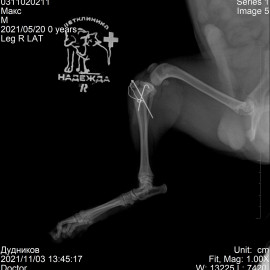

Снимок 2 после операции.